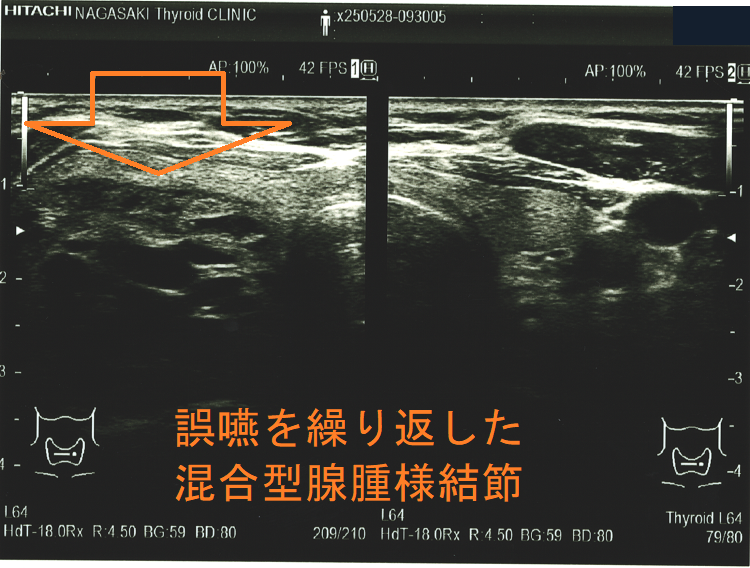

誤嚥を繰り返した混合型腺腫様結節